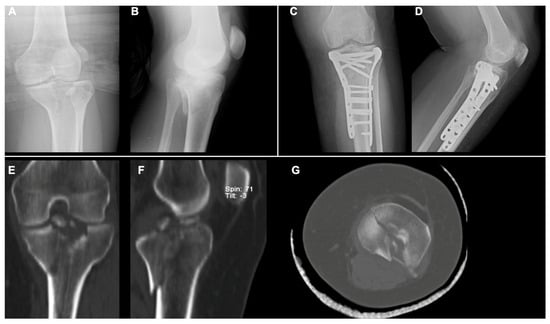

- BCFs (Schatzker V–VI): ORIF with two plates (medial and lateral) and screws.